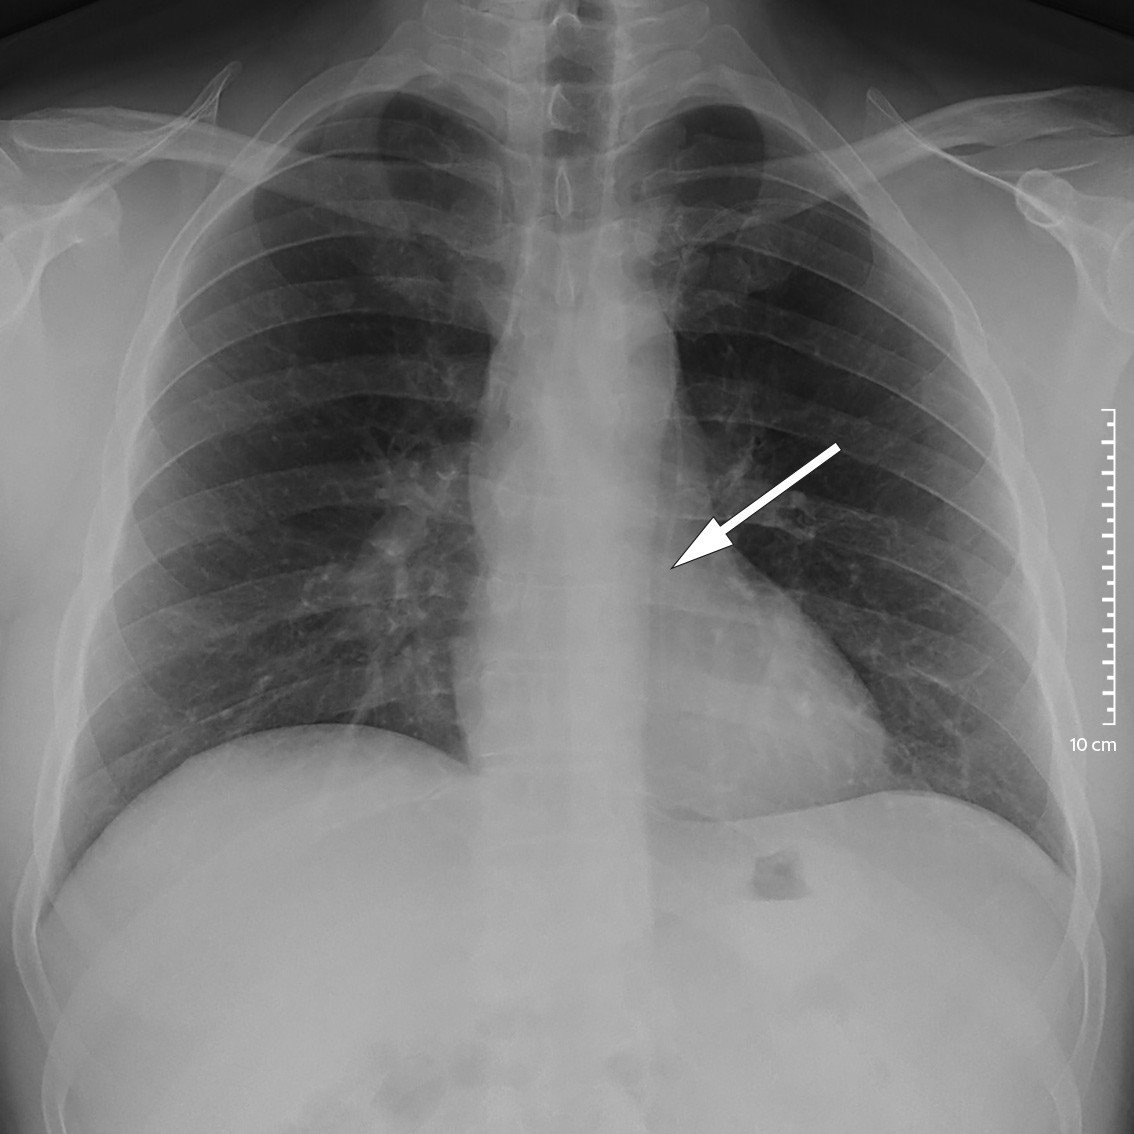

Ved lokalsykehuset var respirasjonen ubesværet, blodtrykket 130/75 mmHg, pulsen 95 slag/min og temperaturen på 39,3 °C. Han var lyssky og nakkestiv. Glasgow Coma Scale (GCS)-skår var 14 med lukkede øyne på grunn av lysskyhet. Blodprøvene viste leukocytter 11,9 × 109/L (referanseområde 3,5–10,0 × 109/L), nøytrofile granulocytter 9,6 × 109/L (1,5–7,3 × 109/L) og CRP 24 mg/L (< 4). Arteriell blodgass uten oksygentilskudd viste hypoksemi med pO2 8,1 kPa (11,0–14,0), men det ble ikke utredet videre pga. hastesituasjon. Blodkulturer og nasofarynksbakteriologi var begge uten senere oppvekst, og han var negativ for pneumokokkantigen i urin. Det ble ikke tatt røntgen toraks. På bakgrunn av sykehistorie med tidligere hjerneabscess ble det gjort CT caput før planlagt spinalpunksjon. CT-undersøkelsen viste en kontrastladende lesjon i høyre temporallapp og tegn på ødem og økt intrakranialt trykk. Intravenøs cefotaksim 3 g × 4 og intravenøs metronidazol 1,5 g × 1 ble igangsatt på mistanke om hjerneabscess, og han ble ikke spinalpunktert. Han ble raskt overflyttet til nevrokirurgisk avdeling ved et universitetssykehus. MR caput samme kveld viste en kontrastladende lesjon med perifokalt ødem i høyre temporallapp (figur 1).

MR caput med kontrast er nødvendig for å stille diagnosen, da det skiller abscess fra andre tilstander som malign tumor, men i praksis vil CT caput ofte tas først (4). Lesjonen framstår på CT som ringformet med kontrastopptak rundt (5). På MR caput med kontrast finner man diffusjonsrestriksjon på diffusjonsvektede sekvenser (diffusion weighted imaging, DWI) og en indre hyperintens og ytre hypointens kant på susceptibilitetsvektede MR-bilder (SWI-magnitude) (6).

MR caput med intravenøs kontrast bekreftet funnet (figur 6). Han ble reoperert dagen etter i narkose med rekraniotomi og fjerning av abscess med kapsel. Pasienten kom seg raskt etter operasjonen uten nevrologiske utfall.